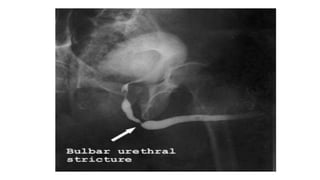

• Stricture

• Extravasation of contrast - due to use of excessive pressure in

• #39 Retrograde Urethrogram showing extravastion of contarst at the site of posterior uretrhal injury